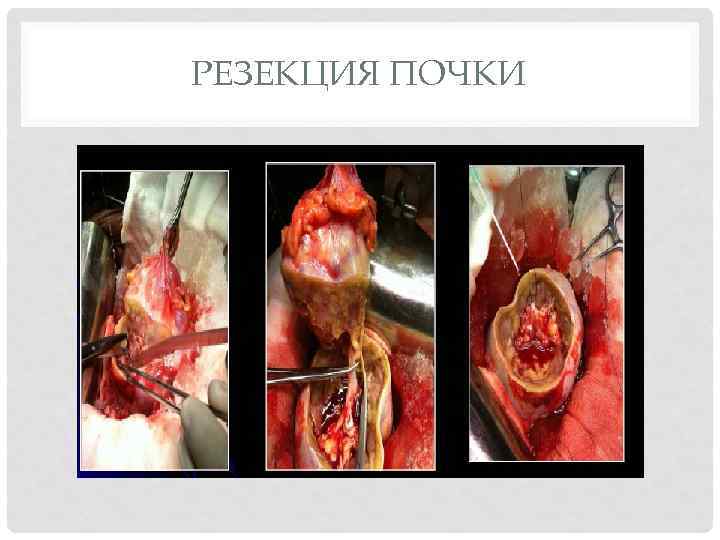

РЕЗЕКЦИЯ ПОЧКИ